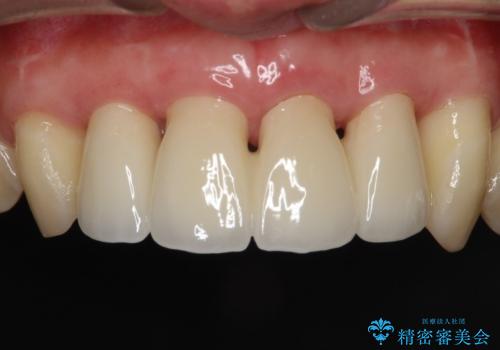

侵襲性歯周炎。前歯の歯周補綴

- 前歯がグラグラすることを主訴に来院されました。

再生治療後、歯周補綴を行っております。

歯周病が進行してしまった歯に対し、再生治療および歯周補綴を行うことで歯周組織の安定を得ることができました。